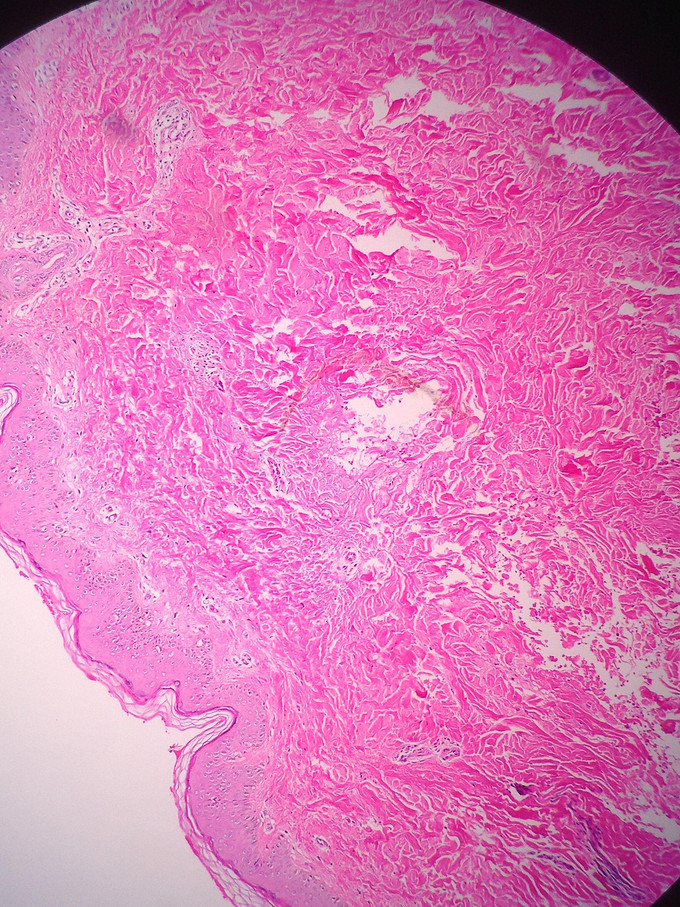

体检:系统检查未见明显异常。皮肤科专科体检:四肢弥漫性淡白色不规则光滑斑片,0.5-2.0cm大小,边界不甚清楚,肢体下垂或用力时,皮疹明显加重,平放或上抬后皮疹部分消失,摩擦后皮疹部分消退(图1)。辅助检查:血、尿、粪常规与心电图无明显异常;皮肤病理(左下肢平放时活检取材)示:表皮正常,真皮内少量毛细血管扩张,少量淋巴细胞浸润,无色素细胞及色素异常。

诊断:Marshall-White综合征 治疗方案:银杏叶片,一日三次,一次一片;治疗一月。皮疹稍好转。